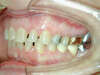

Vues avant le traitement